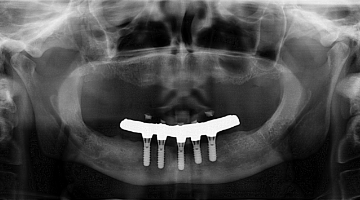

What implant is this?

So, here’s my challenge to you: Can you identify this implant (figure 7)?

Drop me an email at [email protected]!